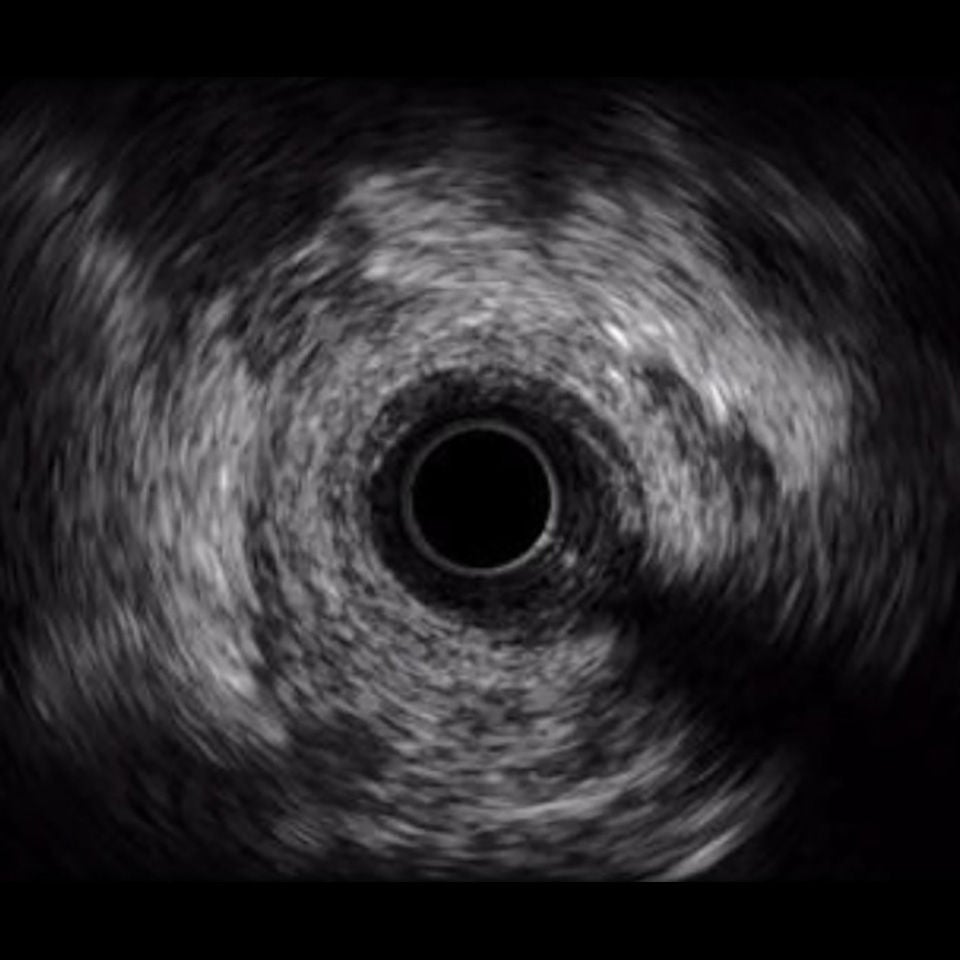

OPTICROSS Imaging Catheter 40 MHz

IVUS image of inside a coronary vessel using the 40MHz Opticross catheter

Axial resolution: 38 µm